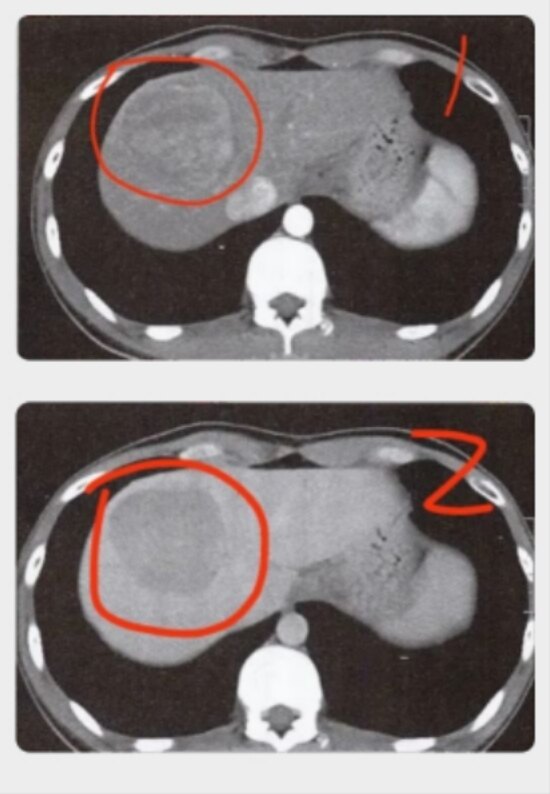

肝血管瘤会转化成肝癌吗?

确诊的肝血管瘤患者通常建议每半年复查一次即可,观察血管瘤的增长速度,如果血管瘤每年增长不超过1cm,通常认为在正常范围内对于快速增长的肝血管瘤或体积较大的肝血管瘤,可以采取外科手术治疗但需要警惕有可能将肝脏恶性肿瘤误...